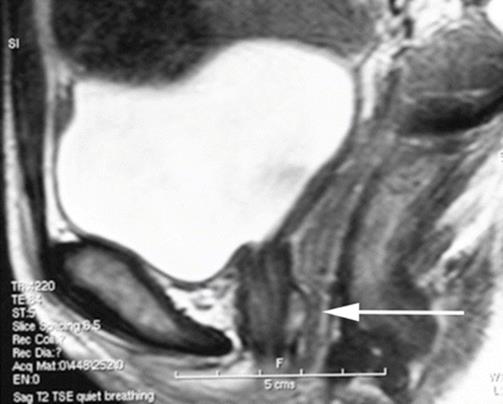

8.13 Large Urethral Leiomyoma Causing Urethral Obstruction

During her second pregnancy, the young patient in Figs. 8.43, 8.44, 8.45, 8.46, 8.47, 8.48, 8.49, 8.50, 8.51, 8.52, 8.53, 8.54, 8.55, 8.56, 8.57, and 8.58 presented with difficulty in voiding, tenderness in the anterior vaginal wall, and the feeling of a mass. Physical examination revealed a large, nontender, elastic, nonmobile mass inferior to the pubic bone. The mass displaced the urethra inferiorly.

Fig. 8.43

Sagittal T2 MRI of the midpelvis reveals a large mass, mostly solid, with areas of necrosis and fluid displacing the anterior vagina and urethra inferiorly. The uterus is normal except for several small fibroids, and the adnexa are normal

Fig. 8.44

An axial MRI shows the replacement and displacement of the urethra by the large mass. Multiple areas of necrosis are seen. The arrows outline the tumor